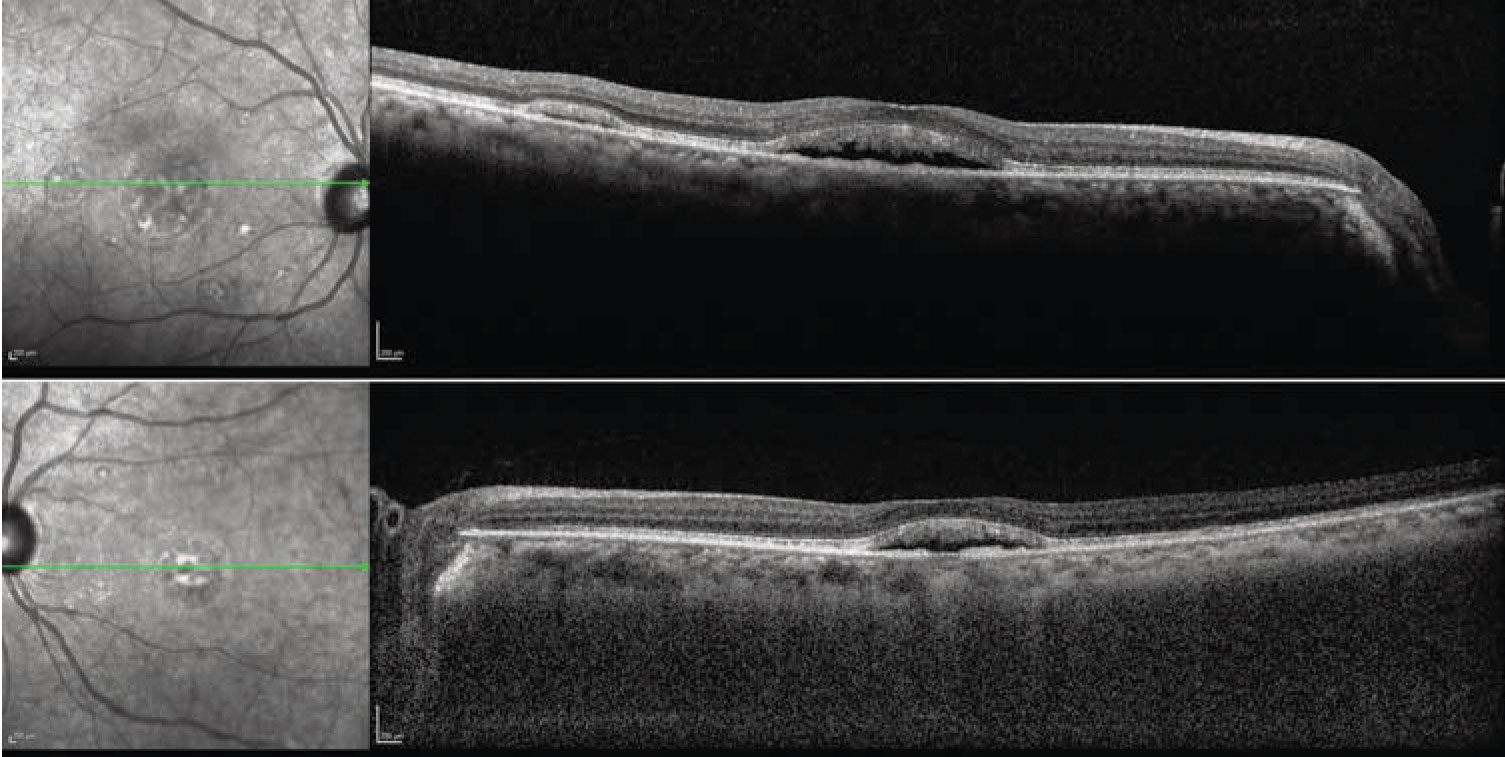

The fundus examination was remarkable for bilateral, multifocal areas of subretinal fluid (SRF) in the macula, including foveal involvement. There were no abnormalities in the periphery (Figure 1). Optical coherence tomography scans demonstrated subfoveal fluid in both eyes with multifocal, smaller collections of SRF. The interdigitation zone was thickened and irregular. With enhanced-depth imaging, the choroid appeared to be not substantially thickened bilaterally (Figure 2).

Given the ophthalmoscopic exam, we pursued further diagnostic imaging. Fundus autofluorescence revealed bilateral areas of hyperautofluorescence that correlated to the accumulation of SRF. We observed no foci of hyperautofluorescence in the periphery. Absent were gravity-dependent fluid shifts, or guttering (Figure 3).

Figure 1. Fundus examination shows multifocal areas of subretinal fluid bilaterally. |